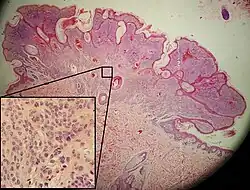

| Dysplastic nevus | Usually a compound nevus with cellular and architectural dysplasia. Like typical moles, dysplastic nevi can be flat or raised. While they vary in size, dysplastic nevi are typically larger than normal moles and tend to have irregular borders and irregular coloration. Hence, they resemble melanoma, appear worrisome, and are often removed to clarify the diagnosis. Dysplastic nevi are markers of risk when they are numerous, such as in people with dysplastic nevus syndrome. According to the National Institute of Health (NIH), doctors believe that, when part of a series or syndrome of multiple moles, dysplastic nevi are more likely than ordinary moles to develop into the most virulent type of skin cancer called melanoma.[19] | _-_crop.jpg) In this case, the central portion is a complex papule, and the periphery is macular, irregular, indistinct and slightly pink. |

Characteristic rete ridge bridging, shouldering, and lamellar fibrosis. H&E stain. Characteristic rete ridge bridging, shouldering, and lamellar fibrosis. H&E stain.

|